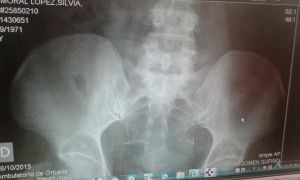

Se trata de las historias de S.M. (cuya radiografía podéis ver acompañando este texto), que tiene un Essure mal colocado.

Pero la ecografía, como el algodón no engaña, el Essure derecho está desaparecido: